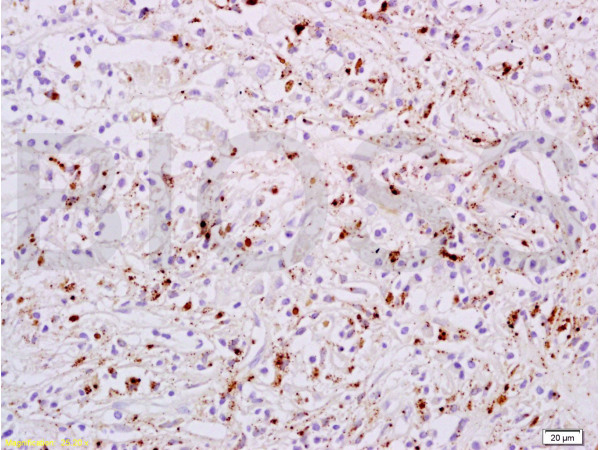

Formalin-fixed and paraffin embedded human liver carcinoma tissue labeled with Anti-phospho-STAT6(Tyr641) Polyclonal Antibody, Unconjugated (bs-1791R) at 1:200 followed by conjugation to the secondary antibody, (SP-0023), and DAB staining